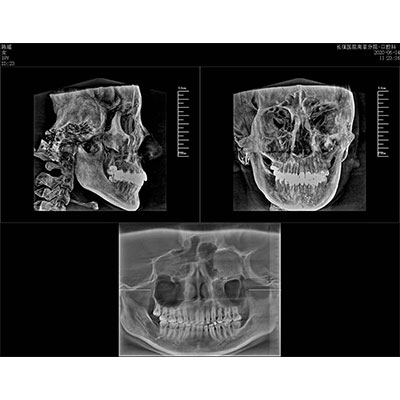

高清口腔三維CT/全景影像 PLX3000A

該款牙科CBCT產(chǎn)品采用動態(tài)平板探測器,獲得三維圖像的同時還具有數(shù)字化全景功能,廣泛應用于口腔頜面外科、正畸科、正頜外科、種植科、牙體科、顳下頜關(guān)節(jié)科等術(shù)前術(shù)后。

專有三維重建算法,可提供任意位置高清斷層影像。

通過三維容積影像,提取高清口腔全景影像。

可同時觀察軸向面、冠狀面和矢狀面圖像,方便臨床診斷。